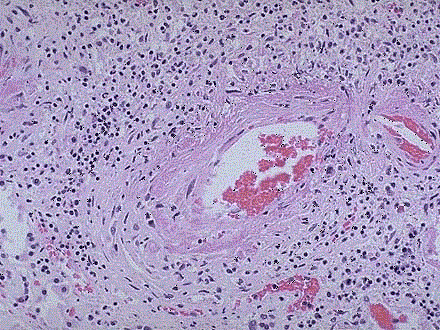

问题 结节性多动脉炎患者肾脏病变镜检如图所示,关于该病说法错误的是 ( )

选项 A.肾脏和胃肠道为最常见受损器官 B.肾梗死常见 C.晚期可出现进行性肾功能衰竭 D.镜下,肾动脉、叶间和弓形动脉呈坏死性动脉炎改变 E.虽有肾损害,但绝大部分患者没有肾损害的临床表现

答案 E